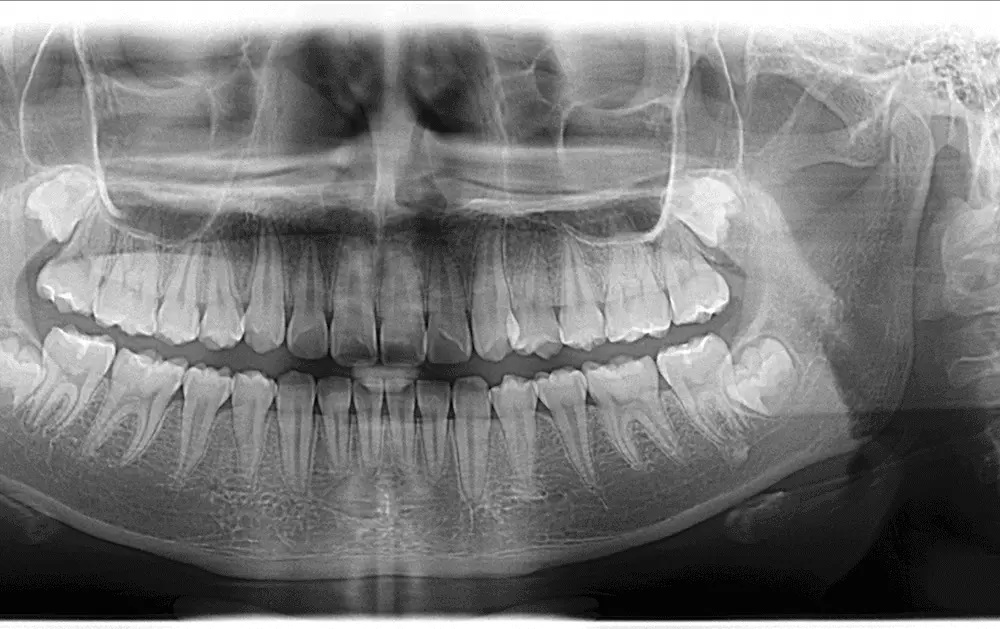

Licówki ceramiczne z wykorzystaniem ceramik szklanych wykonywane są od ponad 20 lat. Charakteryzują się wysoką wytrzymałością mechaniczną. Zapewniają także bardzo dobry efekt funkcjonalny i estetyczny. Przypadek kliniczny stosowania ceramik szklanych w wykonywaniu licówek opisuje dr n. med. Piotr Okoński.